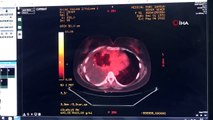

-Kapalı ameliyattan detay

-Genel görüntü